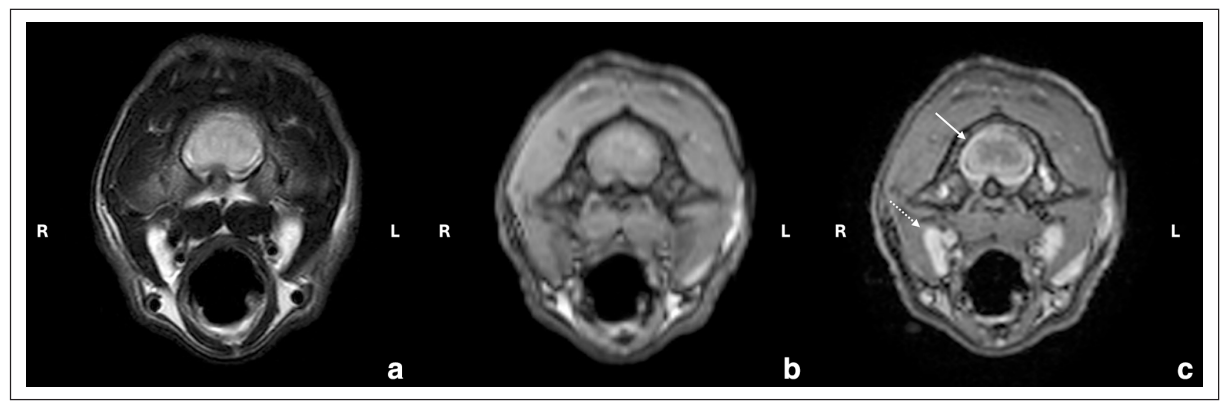

第66天,进行了高场强脑部和颈椎MRI检查。发现延髓至C5的髓内病变、脊髓肿胀(图1)、中度脑室扩大(图2)以及多灶性脑膜增厚且对比增强显著(图3)。肿胀限制了对枕大池的通路,因此需要进行腰椎穿刺而不是寰枕部穿刺以获取脑脊液。

↑ 图3. 颈椎C1水平的横断面图像,(a) T2W,(b) T1W增强前和(c) T1W增强后。脑膜中度增厚且对比增强显著(白箭头),与明显的脑膜炎相符。轻度双侧咽后内侧淋巴结肿大(虚白箭头)。